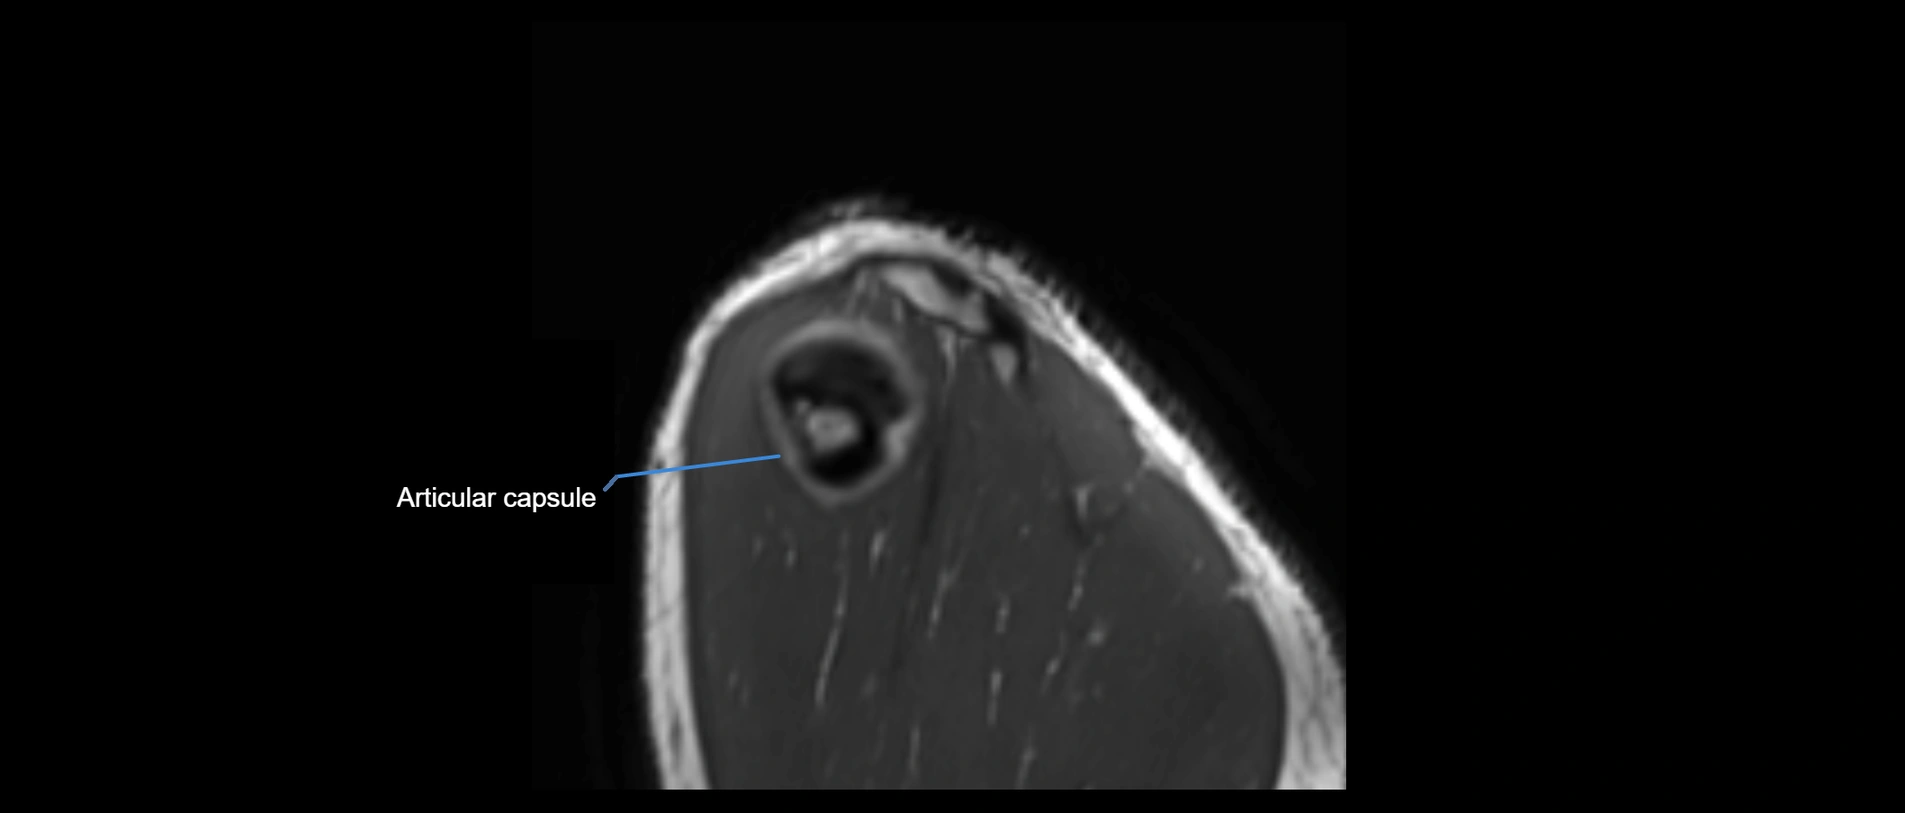

CT image

image

CT Appearance

Non-Contrast CT:

• Ligament: Not directly visualized due to small size and low density.

• Bony landmarks: Lateral clavicle and acromion clearly seen; cortical margins well defined.

• Pathology: Detects fractures, joint subluxation, osteophytes, and degenerative changes.

• Alignment assessment: Evaluates AC joint spacing and clavicular displacement.

Post-Contrast CT (standard):

• Ligament itself: Non-enhancing fibrous band.

• Inflamed capsule or soft tissue: May show enhancement.

• Useful for: Evaluating post-traumatic deformities, ossified ligaments, and chronic AC joint arthropathy.